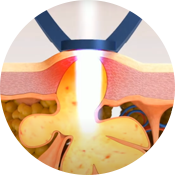

- 1450nm의 파장을 가진 다이오드 레이저로 피지선 주변 염증완화

- 400nm 블루라이트 파장으로 여드름균의 살균효과

- A.T.C.D 냉각 시스템 탑재로 통증없는 편안한 시술

피지선을 위축시켜

피지분비 억제

얼굴 전반적인

피지 분비 억제